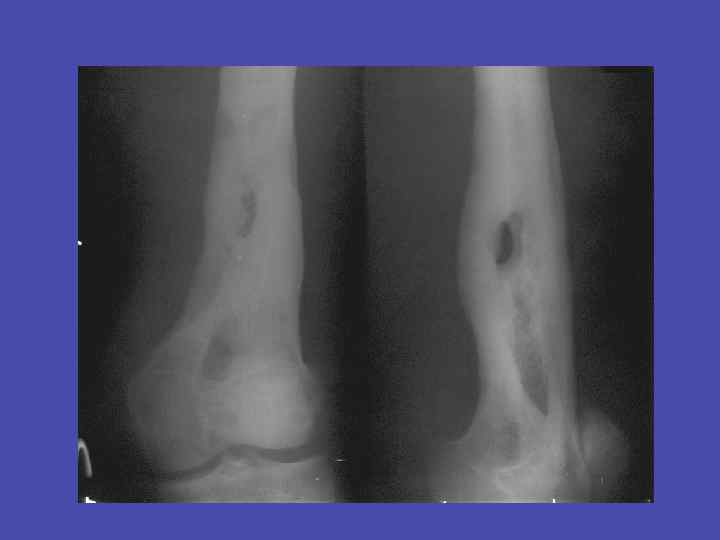

Линейный периостит, деструкция метадиафиза, перфорационные отверстия большеберцовой кости 34

Периостит, деструкция метадиафиза, перфорационные отверстия плечевой кости 35

Перфорационные отверстия большеберцовой кости 36